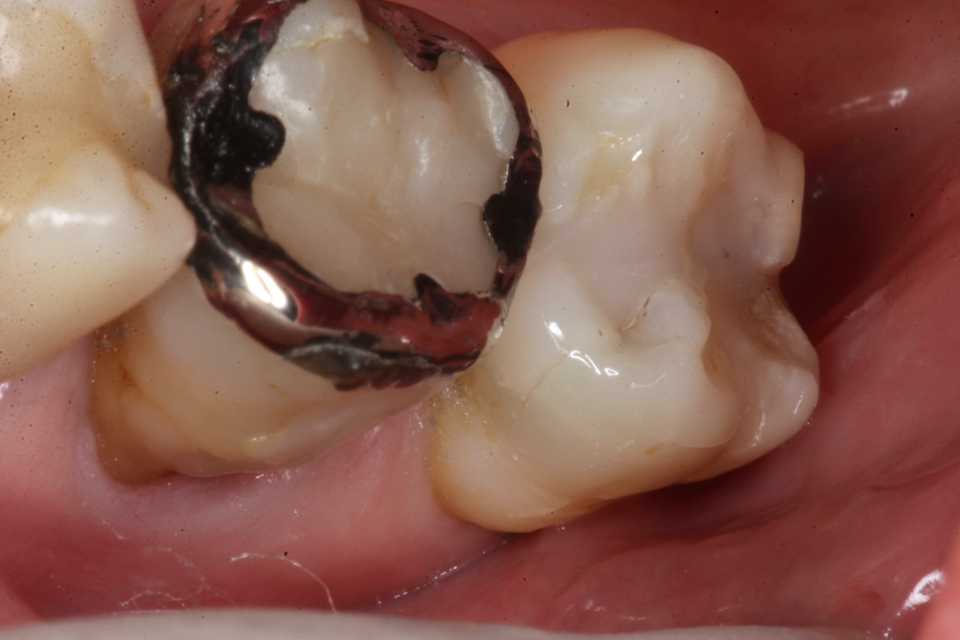

歯茎部カリエス(応力腐食割れ)0.2 2025.08.01

歯茎部カリエス(応力腐食割れ)0.1 2025.07.31

歯茎部カリエス(応力腐食割れ)0.0 2025.07.26